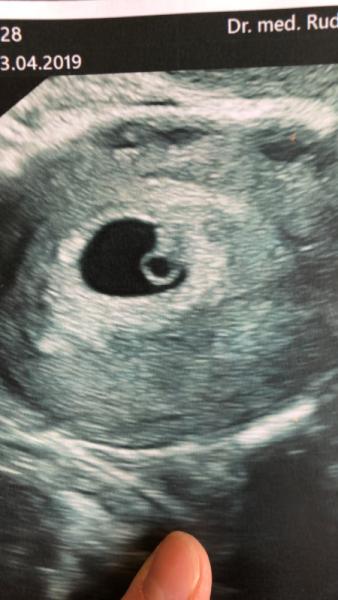

Ich möchte mich jetzt auch offiziell einreihen :) Nach schon einer etwas kritischeren Zeit und einer Woche absoluter Bettruhe, kam ich jetzt vom Arzt wieder. Meinem kleinen Schatz geht es gut und sein Herz schlägt auch Bin heute bei 6 + 5 und freue mich die nächsten Monate mit euch gemeinsam zu verbringen :) Man erkennt jetzt schon ein kleines Miniaturbaby

Bild zu Endlich :) - Forum für Januar - Mamis